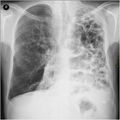

قد يفيد تصوير الصدر بالأشعة السينية والعد الدموي الشامل في استبعاد أسباب أخرى في وقت التشخيص.[52] والسمات المميزة للأشعة السينية هي التمدد الشديد للرئتين، وانبساط الحجاب الحاجز، وزيادة حيز الهواء خلف القص، والأمراض الجلدية، في حين أنها قد تساعد في استبعاد أمراض الرئة الأخرى مثل ذات الرئة ووذمة الرئة أو الاسترواح الصدري.[53] يمكن لصورة الصدر عالية الوضوح باستخدام التصوير المقطعي المحوسب بالأشعة السينية أن تبين توزيع النفاخ الرئوي في جميع أنحاء الرئتين ويمكن أيضاً أن تكون مفيدة في استبعاد أمراض الرئة الأخرى.[11] إذا لم يكن مخططاً لإجراء عملية جراحية، فهذا نادراً ما يؤثر على العلاج.[11] ويتم استخدام غازات الدم الشرياني لتحديد مدى الحاجة إلى الأكسجين؛ ويوصى به لمن يُتوقع أن يكون حجم الزفير القسري لديهم1 أقل من 35%، والذين لديهم تشبع أكسجين محيطي أقل من 92% والذين تظهر لديهم أعراض قصور القلب الاحتقاني.[10] في مناطق العالم التي يشيع فيها نقص مضاد التريبسين ألفا-1، يجب أن يوضع في الاعتبار اختبار الأشخاص المصابين بمرض الانسداد الرئوي المزمن (خاصة من هم دون سن 45 ولديهم نفاخ رئوي يؤثر على الأجزاء السفلية من الرئتين).[10]